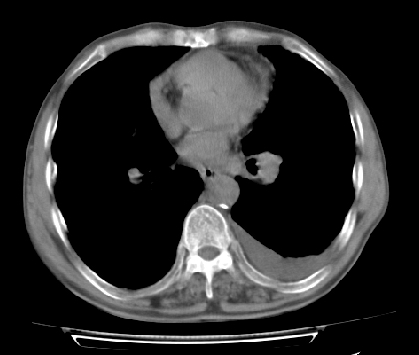

以下是引用ct诊断高手在2009-5-29 13:50:00的发言:[br]考虑左侧中央型肺癌,阻塞性肺炎伴肺不张。纵隔淋巴结转移。慢支 肺间质纤维化肺气肿。左侧胸腔积液。左侧肋骨转移?

以下是引用hhcckk在2009-5-29 14:58:00的发言:[br]左上周围型肺癌,左肺门、纵隔淋巴结转移,左侧胸腔积液,左侧肋骨转移[br]